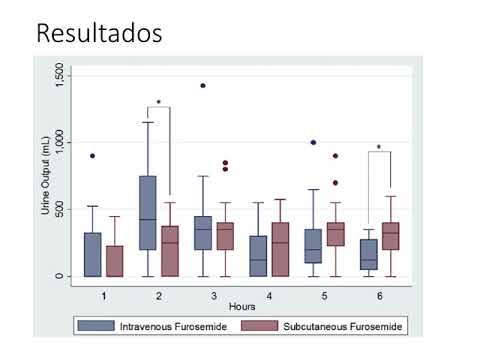

Eficacia de la furosemida intravenosa frente a una nueva formulación. Dr. Guido Vannoni. Residencia de Cardiología. Hospital C. Argerich. Buenos Aires